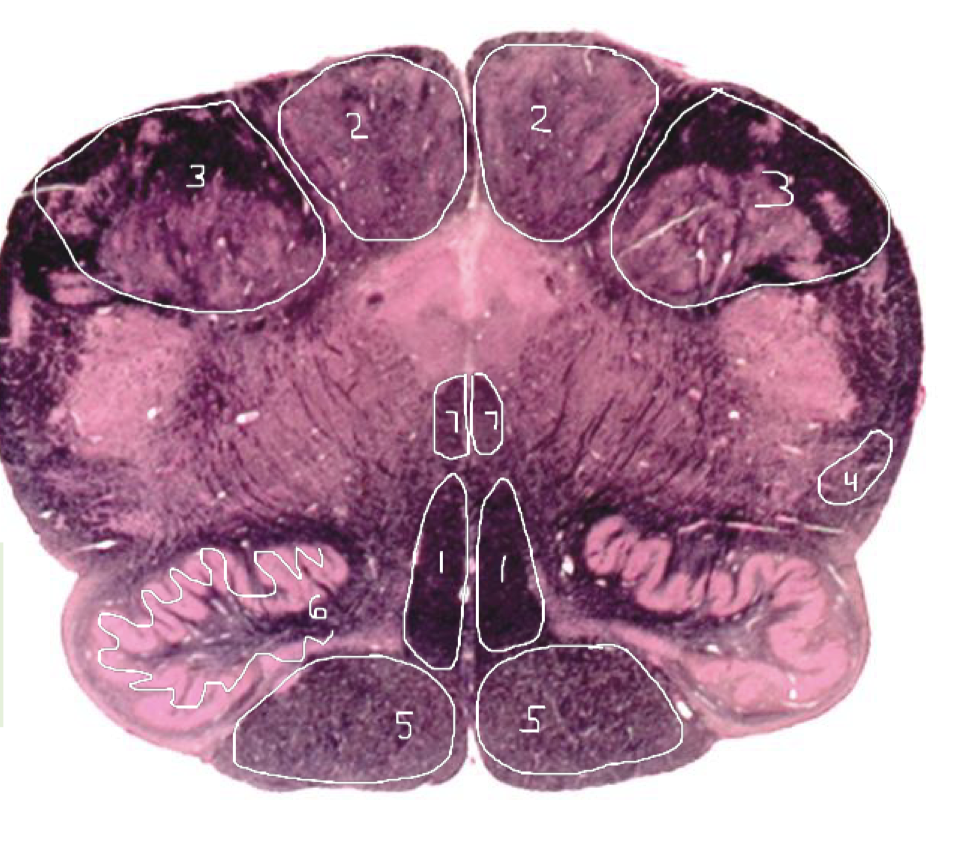

1

Medial Lemniscus - Rostral Pons

2

Spinothalamic Tract - Rostral Pons

3

CST - Rostral Pons

4

Cerebral Aqueduct - Rostral Pons

5

Middle Cerebellar Peduncle - Rostral Pons

6

Superior Cerebellar Peduncle - Rostral Pons

7

Medial Longitudinal Fasciculus (MLF) - Rostral Pons